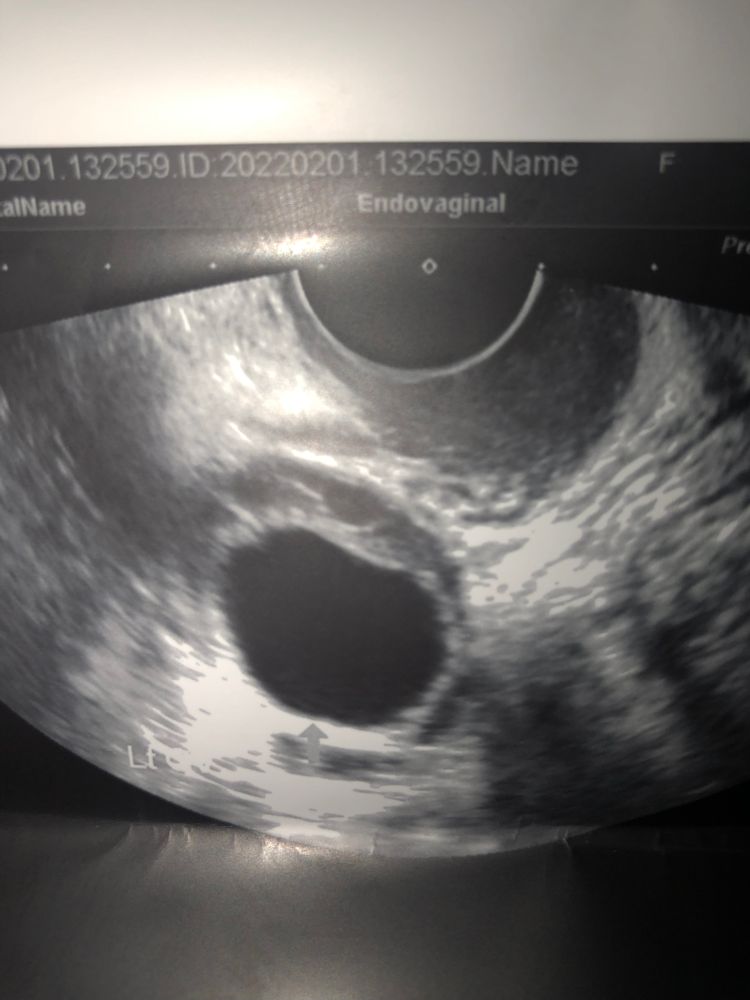

Светлана Никиткова, во вторник сказали фолликулярная киста 22мм,но фото я приложила,похоже на доминантный фолликул,плюс не хочу месячных,лучше Б😁🙏

О, прям моя история))) только мес. нет у меня с 17 декабря. 22.01. на узи все признаки первой фазы - эндометрий 6 мм и в правом яичнике дф 20мм. Гин. сказала "жди М и сдавай анализы на гормоны" Вот до сих пор жду чем история закончится🤷‍♀️ на след нед. опять пойду, если не придут. Так что получается возможно что новый цикл без М. А на фото всё верно ДФ!

На УЗИ предовуляторный ДФ, по моему даже уже в процессе О. ЖТ может появится и через 3 суток после О. Судя по размерам эндика, ДФ и жидкости овуляция была. Читала про новые циклы без М - нечем там менструировать было. Нет эндика - нет М.